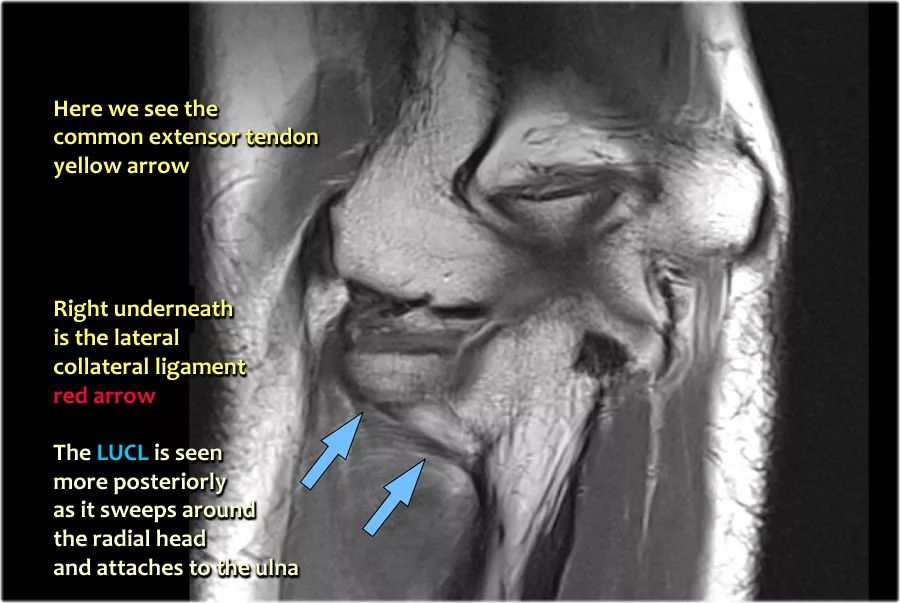

当您寻找桡侧副韧带时,首先要尝试识别常见的伸肌腱,因为在它下面你会发现桡侧副韧带(黄色箭头)。

当你向后走时,你会看到LUCL--侧面尺侧副韧带,它在桡骨头后面扫过(白色箭头)。环形韧带通常难以与RCL区分开,但有时可以在矢状MR-关节造影上识别。

我们可以从连续的冠状位MRI图像观察。